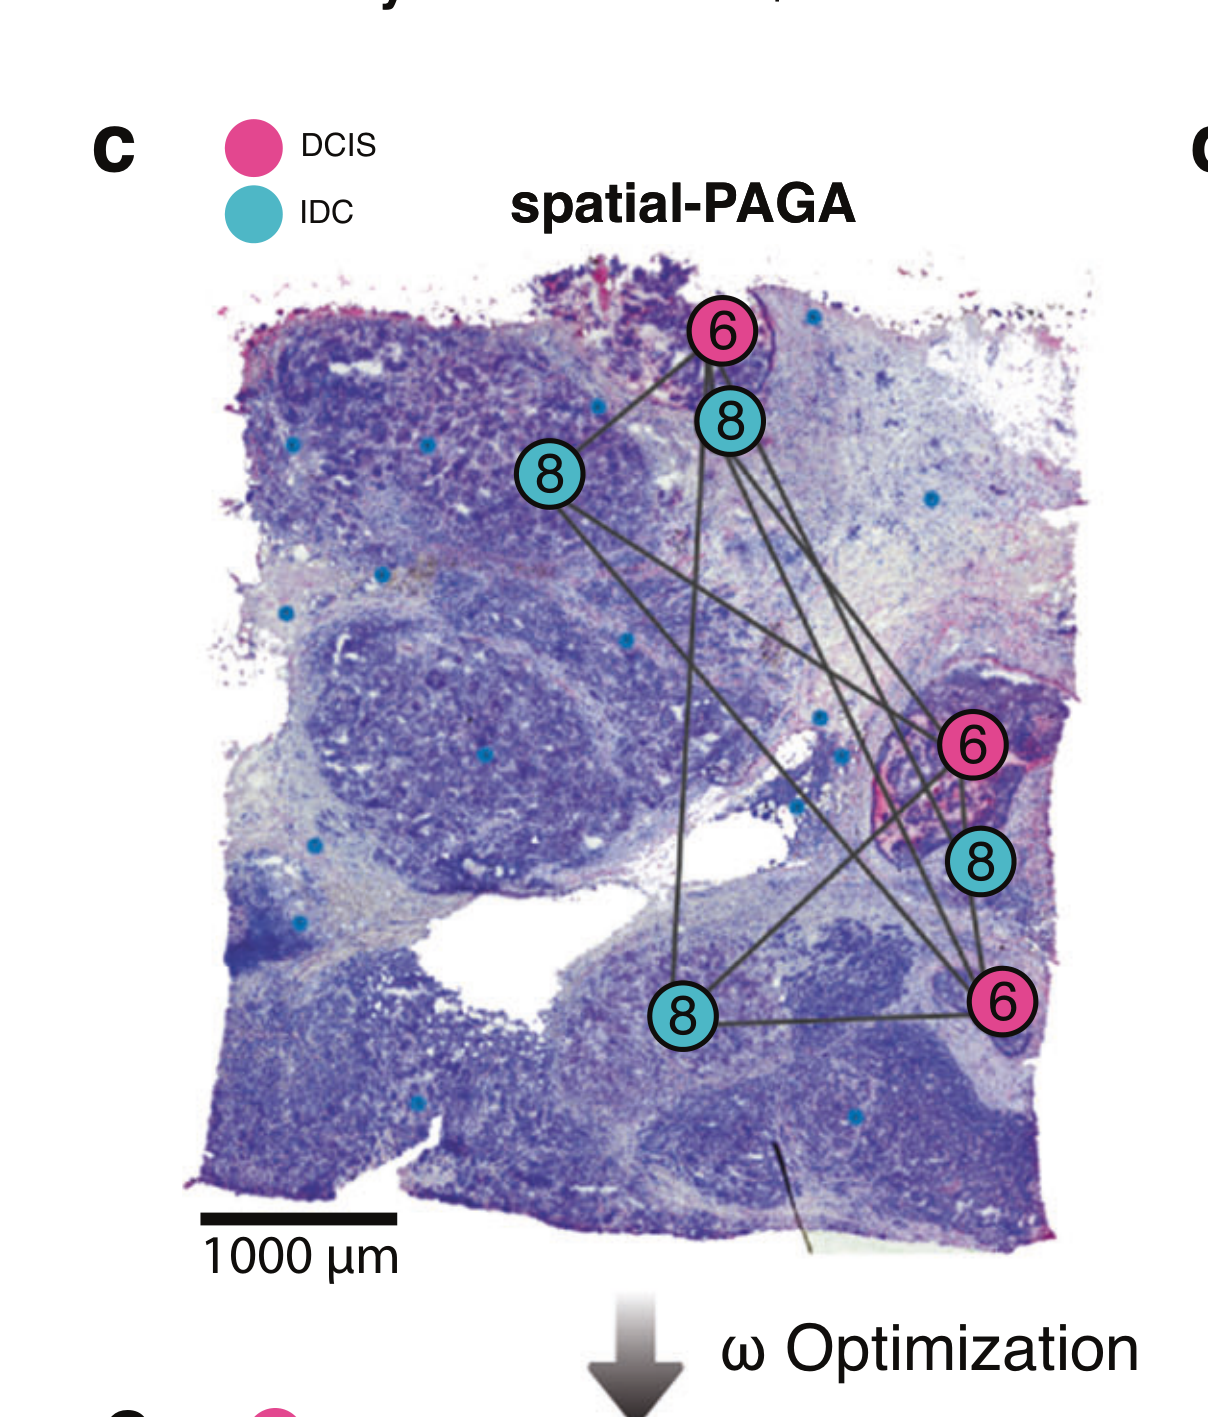

Zohora F.T. et al. - 2025

CellNEST reveals cell–cell relay networks using attention mechanisms on spatial transcriptomics

Condition Dimension

Categorical

Data Components

Gene Expression Matrix

Data

Modality

Sequencing-based

Resolution of observation

Multi-cellular

Visualized Elements

FeatureObservation

Biological

Tissue

Abstraction

Partial

Chart Type

HexplotScatterplot

Communicative/Contextualization

Reference structure

Comparative Design

Juxtaposition : Small multiples

Layout

Spatial : Physical

Scalability Strategy

None (Item-level)

What is the spatial distribution of disease subtypes?

What is the tissue morphology and architecture?